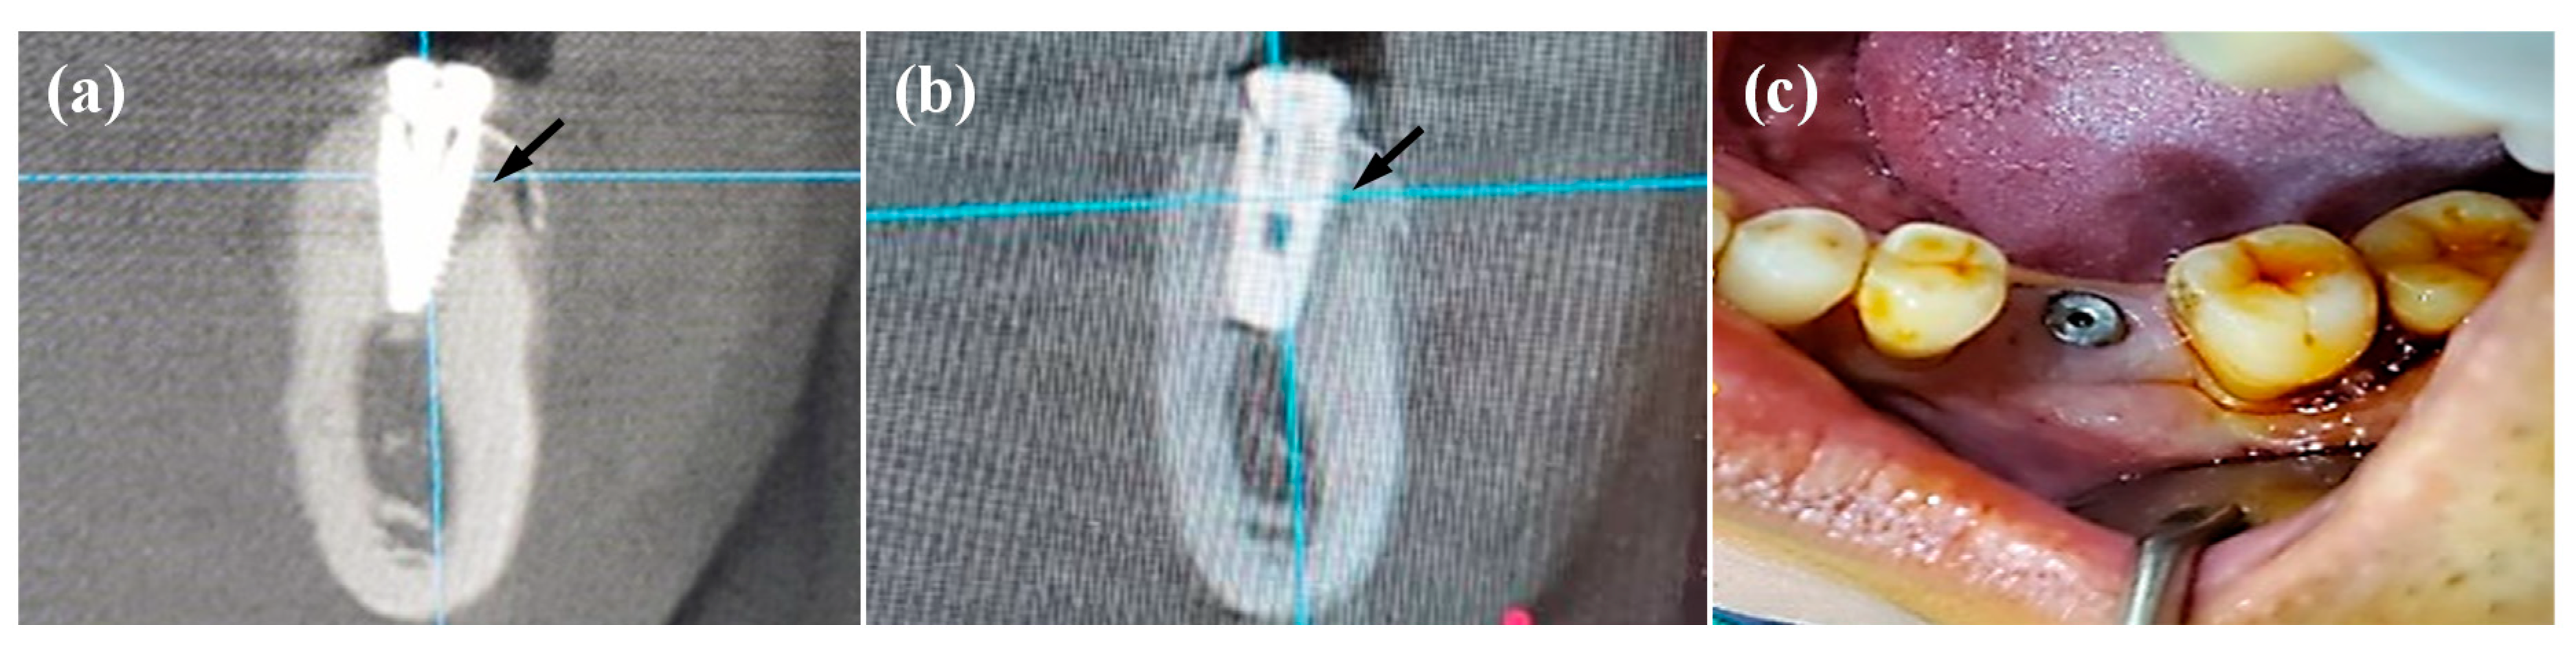

3.4. Clinical Evaluations of the IDCT-Modified Ti Implant